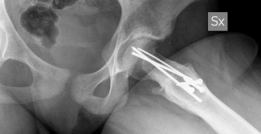

Comprehensive radiographic evaluation is mandatory. Standard imaging includes an anteroposterior view of the pelvis and a cross table lateral view of the affected hip. The frog leg lateral view is strictly contraindicated in unstable slips due to the risk of exacerbating the displacement and causing iatrogenic vascular injury.

Advanced imaging is heavily relied upon in contemporary practice. Magnetic Resonance Imaging is utilized to assess the pre operative perfusion status of the femoral head. T1 weighted and short tau inversion recovery sequences, often supplemented with gadolinium contrast, can identify pre existing ischemia. A pre operative diagnosis of avascular necrosis fundamentally alters the surgical discussion and prognosis. Computed Tomography with three dimensional reconstruction is occasionally utilized to quantify the exact degree of retroversion and the volume of the metaphyseal step off, aiding in the spatial conceptualization of the required osteotomy.